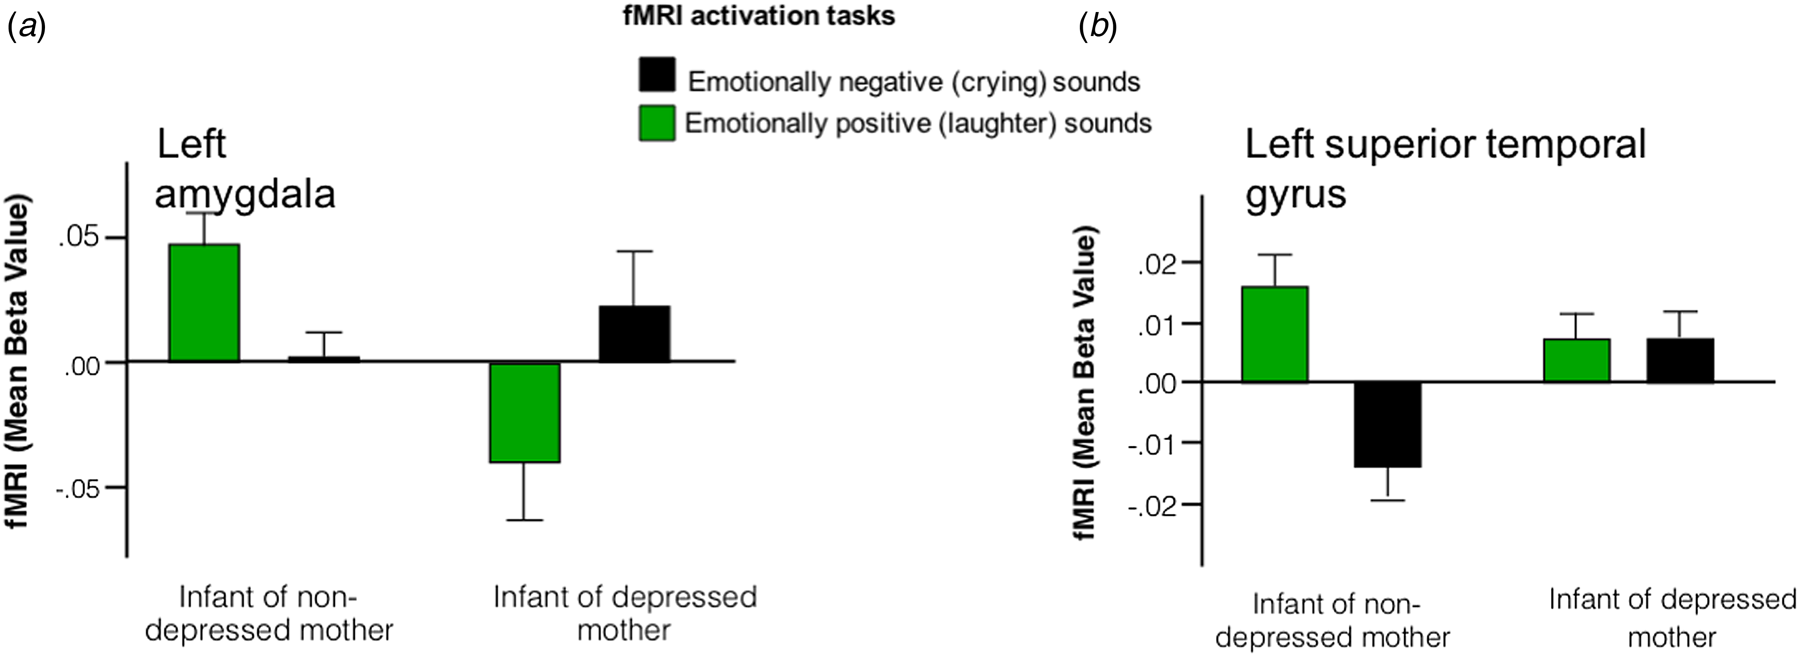

Interaction plots permitted statistical disentanglement of the conditions [i.e. positive (laughter) or negative (crying) valence sounds] in the clusters where the group differences were arising. We found a greater activation to emotionally positive contrasted with emotionally negative sounds in infants unexposed to PMD. Conversely, exposure to PMD was associated with greater (or unchanged) activation to emotionally negative contrasted with emotionally positive sounds in the clusters identified (Fig. 2).

Fig. 2. Interaction plots suggest that infants born to non-depressed mothers exhibit hyper-activation in response to emotionally positive sounds, whereas infants born to depressed mothers exhibit hyper-activation in response to emotionally negative sounds in regions including (a) left amygdala and (b) left superior temporal gyrus.

Our findings indicate that infants exposed to PMD exhibit differences in activation within a frontal-limbic neural network. More specifically, we report, for the first time, that infants born to mothers with PMD exhibit greater activation in response to emotionally negative sounds (crying), whereas infants unexposed to PMD demonstrate greater activation in response to emotionally positive sounds (laughter) (Fig. 1a–c). The finding of a differential response to positive and negative valanced sounds by 3–6 months old may have significant implications for our understanding of neural mechanisms that underpin the increased risk for later-life depression in this population. Whilst it was beyond the scope of the current study to assess this risk, we aim to follow-up our cohort longitudinally for later behavioural measures of depression.

The direction of findings within subcortical structures was consistent with our a priori hypothesis, and studies in people with MDD (Beesdo et al., Reference Beesdo, Lau, Guyer, McClure-Tone, Monk, Nelson and Pine2009; Fu et al., Reference Fu, Williams, Cleare, Brammer, Walsh, Kim and Bullmore2004; Siegle et al., Reference Siegle, Thompson, Carter, Steinhauer and Thase2007; Surguladze et al., Reference Surguladze, Brammer, Keedwell, Giampietro, Young, Travis and Phillips2005; Zhong et al., Reference Zhong, Pu and Yao2016), and older children born to mothers with PMD (van der Knaap et al., Reference van der Knaap, Klumpers, El Marroun, Mous, Schubert, Jaddoe and Fernandez2017). However, the direction of activation in the prefrontal cortex (PFC; i.e. orbitofrontal cortex, and IFG) was opposite to our a priori hypothesis. In older subjects with depression, increased amygdala activation to negatively valanced stimuli is associated with reduced PFC activation. This is understood to be driven by inhibitory connections between the amygdala and PFC. It has previously been reported that these inhibitory connections do not fully develop until adolescence (Silvers et al., Reference Silvers, Insel, Powers, Franz, Helion, Martin and Ochsner2017), which could partly account for the synchronous activity in these regions reported in the infants studied. Further, a recent resting-state fMRI study, using dynamic causal modelling, has reported a stronger excitatory influence from the amygdala to the PFC, and a weaker excitatory influence from the PFC to the amygdala, in PMD-exposed infants compared with controls (Cha et al., Reference Cha, Posner, Roy, Peterson, Gustafsson and Raffanello2017). We, and others, have also reported a positive correlation between prenatal stress and fractional anisotropy of the white matter tract linking these regions (i.e. uncinate fasciculus) in neonates (Rifkin-Graboi et al., Reference Rifkin-Graboi, Meaney, Chen, Bai, Hameed, Tint and Qiu2015) and children (Sarkar et al., Reference Sarkar, Craig, Dell'Acqua, O'Connor, Catani, Deeley and Murphy2014). Importantly, a recent resting-state fMRI study, in 6-month-old infants exposed to PMD symptoms, has found that aberrant connectivity between the amygdala and PFC was independent of postnatal depression scores (Qiu et al., Reference Qiu, Anh, Li, Chen, Rifkin-Graboi, Broekman and Meaney2015). These findings lend further support to a growing consensus that the prenatal environment plays a critical role in the development of neural networks involved in emotion processing. While the task-based fMRI approach used in our study permitted us to take the next step and explore the interaction between this network and emotion-processing, interpretation of our findings remains unclear. In particular, it is unclear whether emotions construed by adults as happy (e.g. laughter) or sad (e.g. crying) are perceived similarly by 3–6 months old infants.